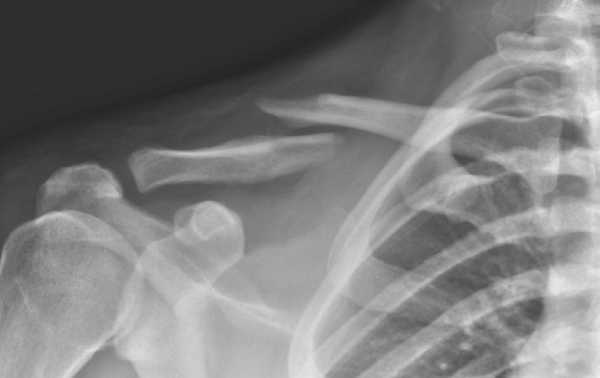

При сомнениях в постановке диагноза возможно проведение рентгенографического обследования или томографии с помощью компьютера.

Дальнейшие мероприятия проводятся в условиях медицинского учреждения. При помощи рентгенографии врач травматолог оценивает характер перелома, тяжесть повреждений и возможное наличие осложнений. Затем выполняется дальнейшая иммобилизация, необходимая для более быстрого и полного заживления. При необходимости врач выполняет репозицию (сопоставление) отломков с их последующим обездвиживанием.

При осмотре обращают на себя внимание деформация в виде припухлости и нередко выпячивание под кожей концов отломков, а также следы кровоизлияния. При ощупывании, которое довольно болезненно, легко обнаруживают концы сместившихся отломков. Плечевой сустав на стороне перелома смещен вниз и чуть вперед, голова наклонена в сторону повреждения.